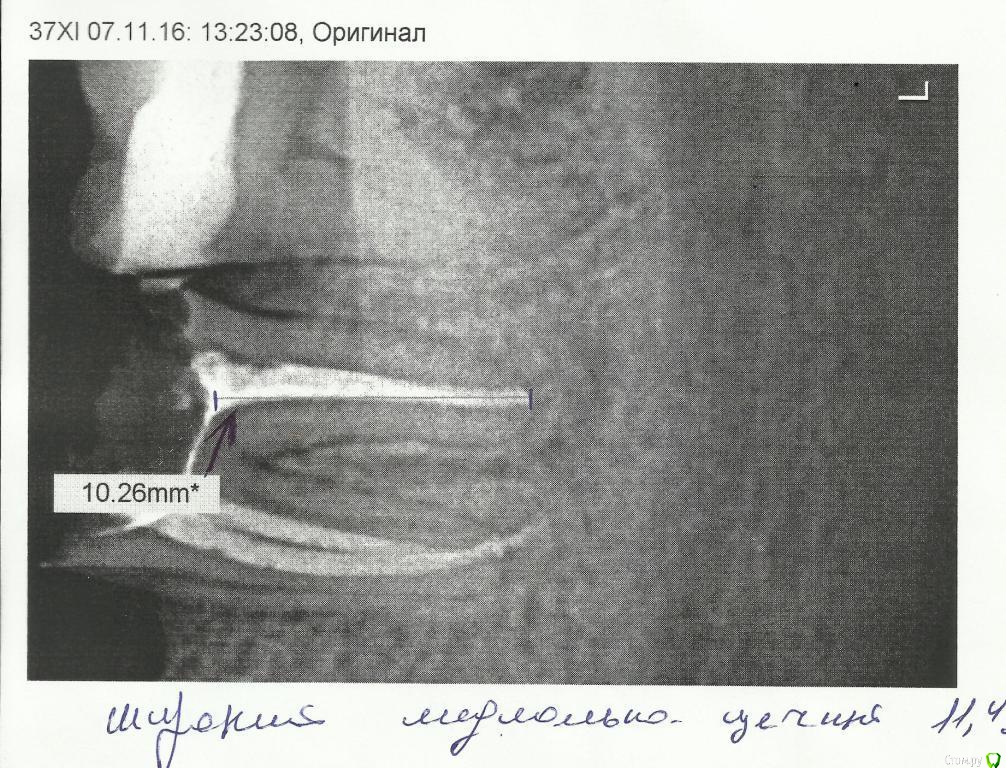

Некий Опубликовано 27 апреля, 2017 Поделиться Опубликовано 27 апреля, 2017 Добрый день!Ранее ношенные "мосты" прохудились и ушли в утиль.Сейчас стоит вопрос принятия "правильного" решения.ОПТГ был сделан еще в ноябре 16г.С тех пор произошли изменения:47 - удален. Заживал очень долго. Несколько раз удалялись секвестры.45 - делается под вкладку. Снимок прилагаю.37 - был сильно разрушен. Восстановлен ниже уровня десны на 3 штифтах. Снимок до восстановления.Доктор предлагает 2 "моста": 34-37 и 45-48. Напрягает состояние 37 и 45 зубов.1. Не получу ли в самое ближайшее время после установки мостов проблемы?2. Не сильно ли углублен канал под вкладку у 45го? Затемнение под корнем - это ни какая-либо проблема?3. Какие еще варианты могут быть при данной ситуации? Большое спасибо за Вашу помощь! Ссылка на комментарий